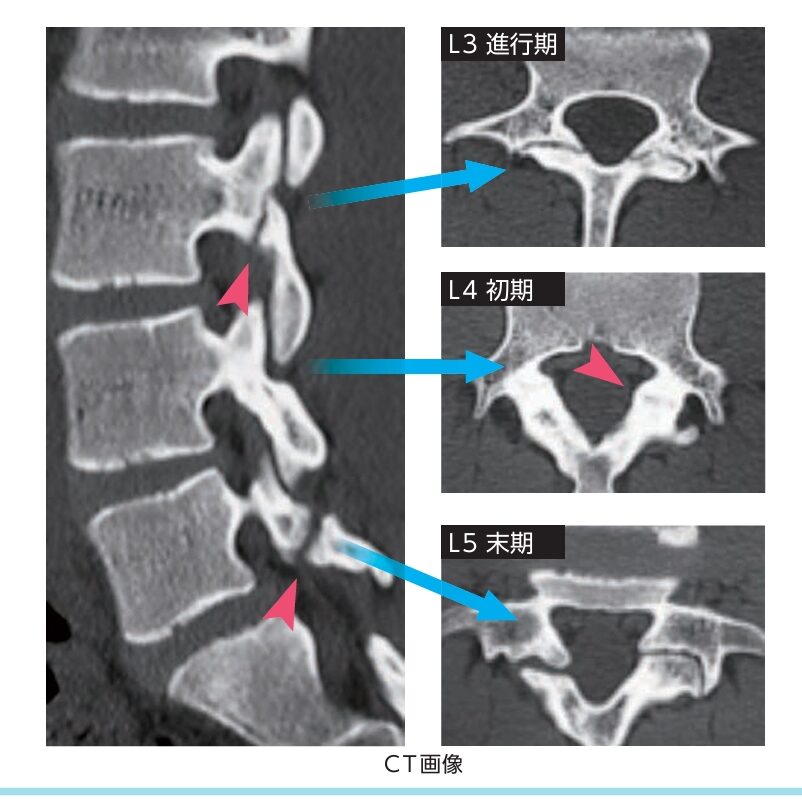

CTというレントゲンの輪切りの詳しい検査でも発症初期は診断難しく発症後1か月で分離しだすと診断可能です。

CTはレントゲンと同じ放射線の検査ですがレントゲンより詳しく輪切りで何十枚も撮影して詳細に見えるようになります。

CTでは初期は診断難しいことも多く進行期(発症後1-2か月以降)で診断可能です。